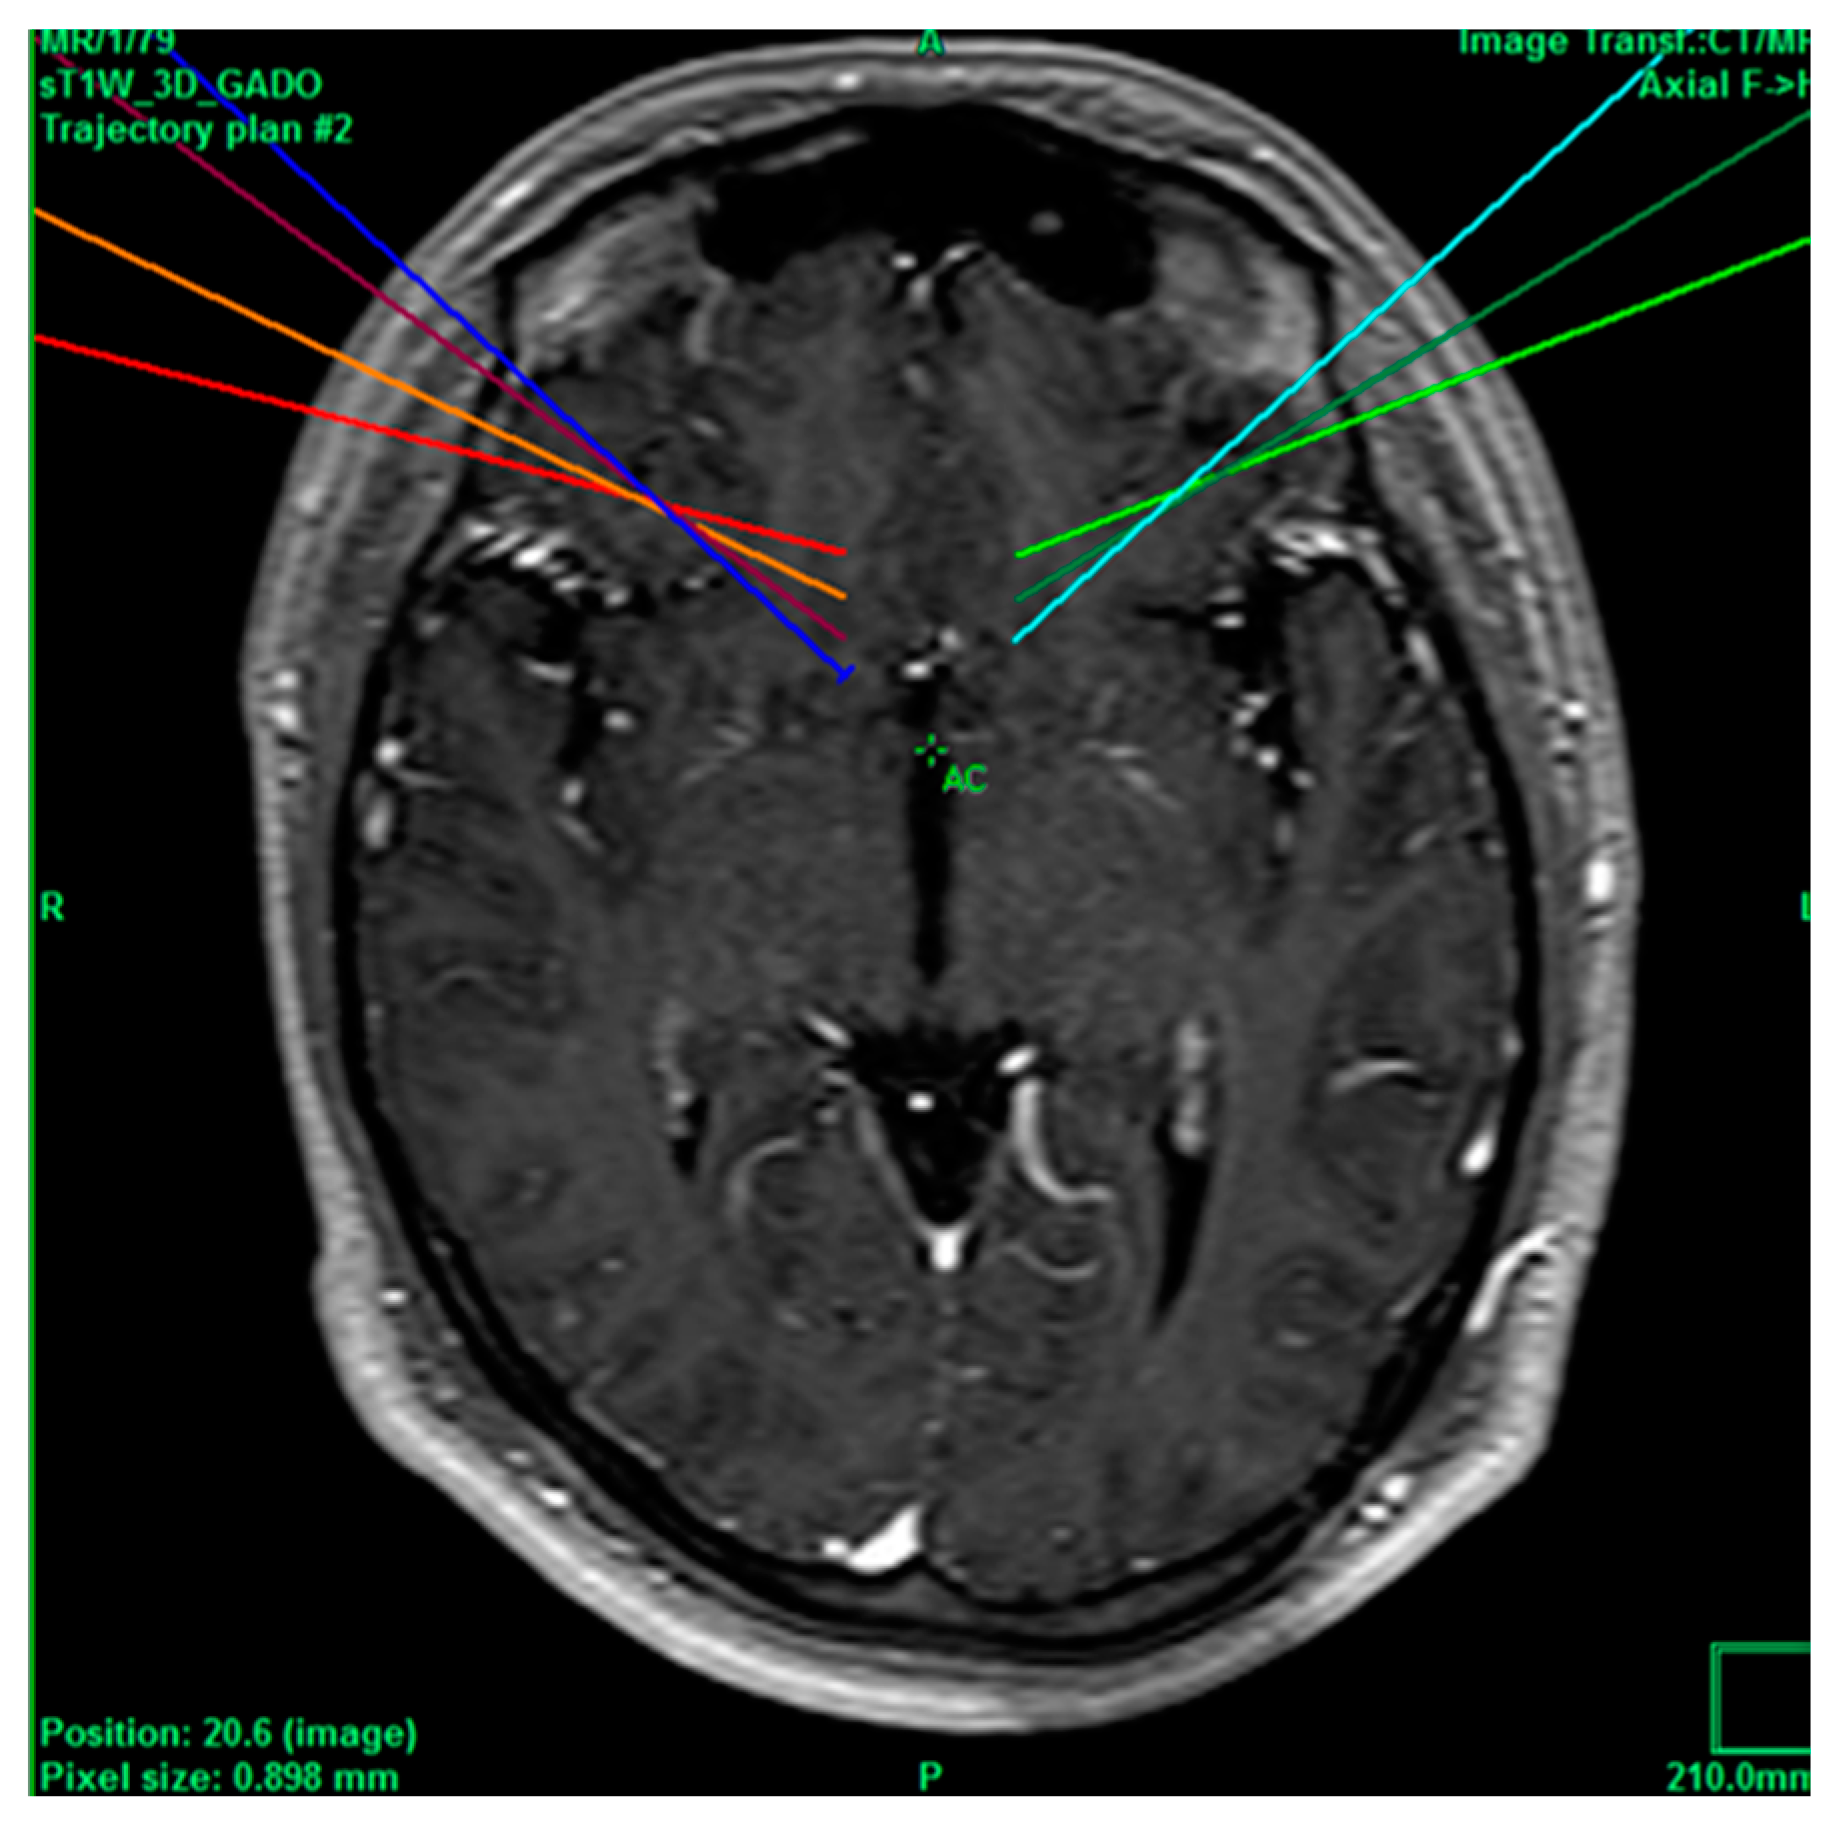

Figure 7.

Projection of cingulotomy from patient 6.